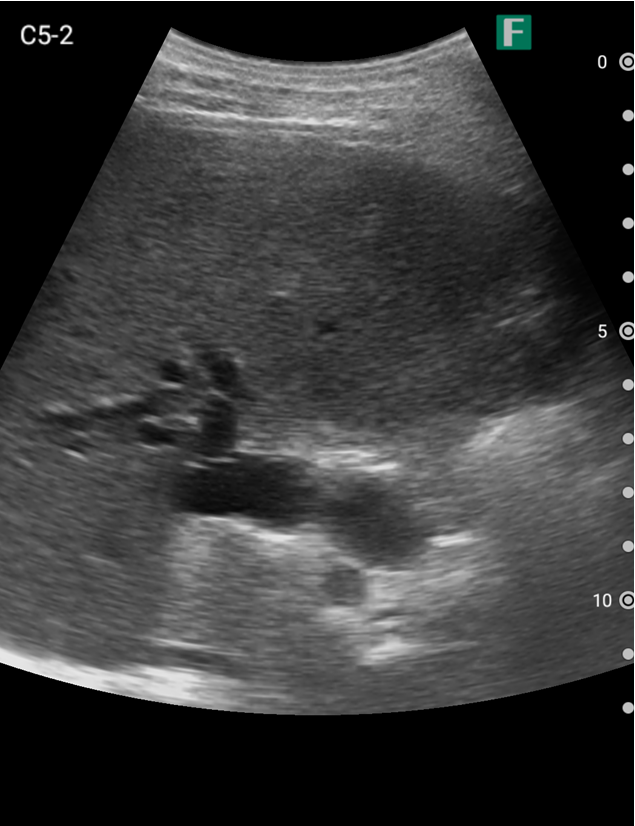

もう一つは入院患者様に対しての具体的な使用事例を紹介します。朝の回診の際にiViz airを使用し、例えば腹水のある患者様を診た際は、「今日は水の量が少なく、そこまでお腹は張ってないですね」、「今日はここに水が溜まっているんですけど、昨日より少ないですよ」など、日々の状態を患者様ご本人に伝えるようにしています。スマホで実際の画像も簡単にお見せできるので、患者様に実際に見ていただくことで少しでも不安を和らげてもらえるように心がけています。

そうして積極的に話をすると、不安そうな表情をする患者様はあまりいらっしゃらない印象を受けています。iViz airがあると患者様と会話をするきっかけにもなるため、コミュニケーションツールとしても実用的だと感じた事例でした。

他にも、iViz airの利点と考えるのは、「答え合わせ」に活用できる点です。朝の回診の際、担当している入院患者様にエコーを当て画像所見を記録します。同日の午後に長沼先生が同患者様をエコーで検査をする現場に立ち合わせて頂き、朝自分が記録した所見の再現性について確認します。

長沼先生がどのように超音波検査を進めるのかを見学しつつ、朝自分が記録した所見についての確認・疑問点など質問をさせて頂きます。それに対して長沼先生からその場でフィードバックを頂き、その過程を繰り返すことで自身の理解度が深まっていくのを強く感じました。